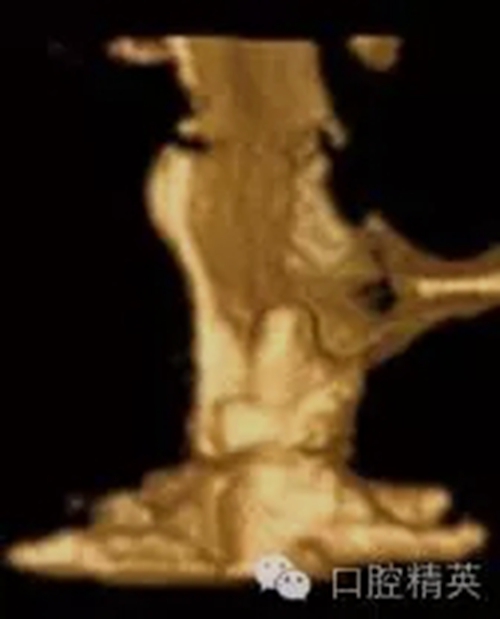

圖1c:術(shù)后用ICATCBCT進(jìn)行三維立體效果再現(xiàn),顯示種植體穿入上頜竇的實(shí)踐情況

圖5c:CBCT三維立體效果再現(xiàn)顯示了25號(hào)牙處嚴(yán)重的頰側(cè)骨板裂開。

口腔種植各種失敗模式的病因探查